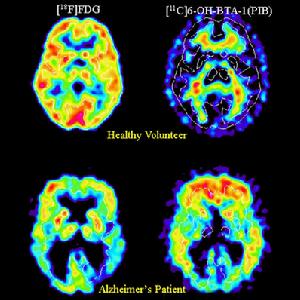

隨著影像學技術的迅速發展,確定腫瘤內不同亞群細胞具有不同克隆源性氧飽和度、增殖率及放射敏感性的空間分布已成為可能。結合這些數據與逆向治療計畫系統及調強手法,在治療前預計治療增益比已提到議事日程上。